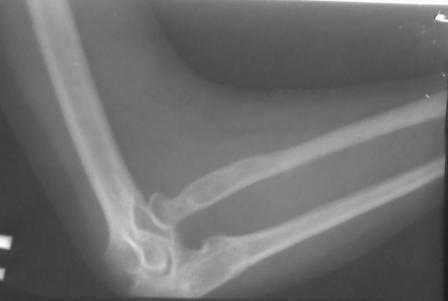

Уважаемые Коллеги! Добрый вечер! Обратилась девушка 18-лет, с жалобами на деформации обоих локтевых суставов, больна с рождения. Оба локтевых сустава в положении сгибания под углом 145гр., дальше разгибание нет за счет укороченных и натянутых м/тканей по передне-наружной поверхности л/сустава. Сгибание полное. но при сгибание предплечья супинируется а при разгибание пронируется,при фиксированным п/плечье ротационных движений нет.Со стороны костно-суставной системы других обл. я патологию не находил. В 2001 г. оперирована лев.рука в одном из центральном институте, со слов вывых был вправлен открыто и фиксация аппаратом Илизарова, после операции рука не сгибалась и ротационных движений не было, что очень ей мещало, после усиленных ЛФК наступило релюксация и движение стало лучше, т.е. как прежная. Фото и Р-снимки прилагается.

Снимки недостаточно информативны ( может быть не все сообщения пришли), рассматривать конфликт проксимального лучелоктевого сочленения невозможно без картинок дистального отдела. Глядя на представленные снимки и предъисторию открытого вправления с рецидивом вывиха, создается впечатление о диспропорции длины локтевой и лучевой костей, врожденном отсутствии аннулярной связи, удерживающей проксимальное лучелоктевое сочленение. Я бы посоветовал сделать снимки предплечья полной длины, включающих дистальное и

проксимальное л.л. сочленения и исходя из этого можно планировать вмешательство: как вариант при обнаружении диспропорции - укорачивающая

остеотомия луча с пластикой связки, если интраоперационно сохраняется тенденция к вывиху.

Врожденный вывих головки лучевой кости является одной из часто встречающихся аномалий локтевого сустава. В большинстве встречаются двухсторонние вывихи и передние.